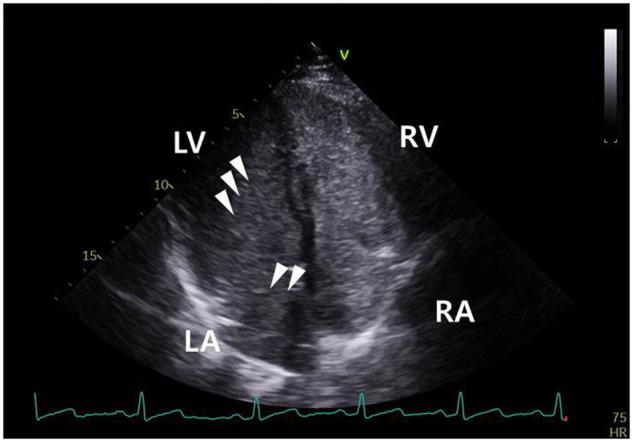

Countless uninvited guests in left atrium.